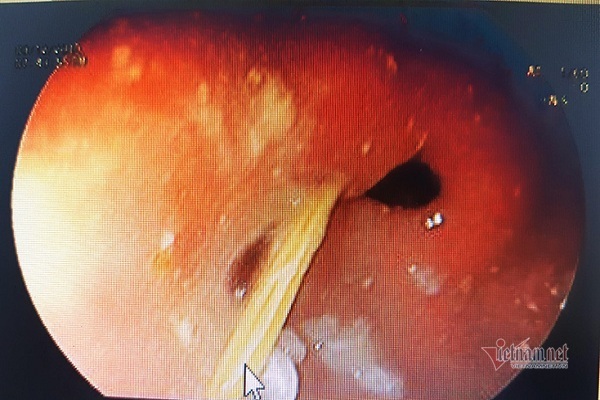

Nam bệnh nhân bị ung thư thực quản nhưng xin về nhà uống thuốc nam. Sau 2 tháng, khối u phát triển to, thậm chí còn xâm lấn, gây thủng dạ dày.